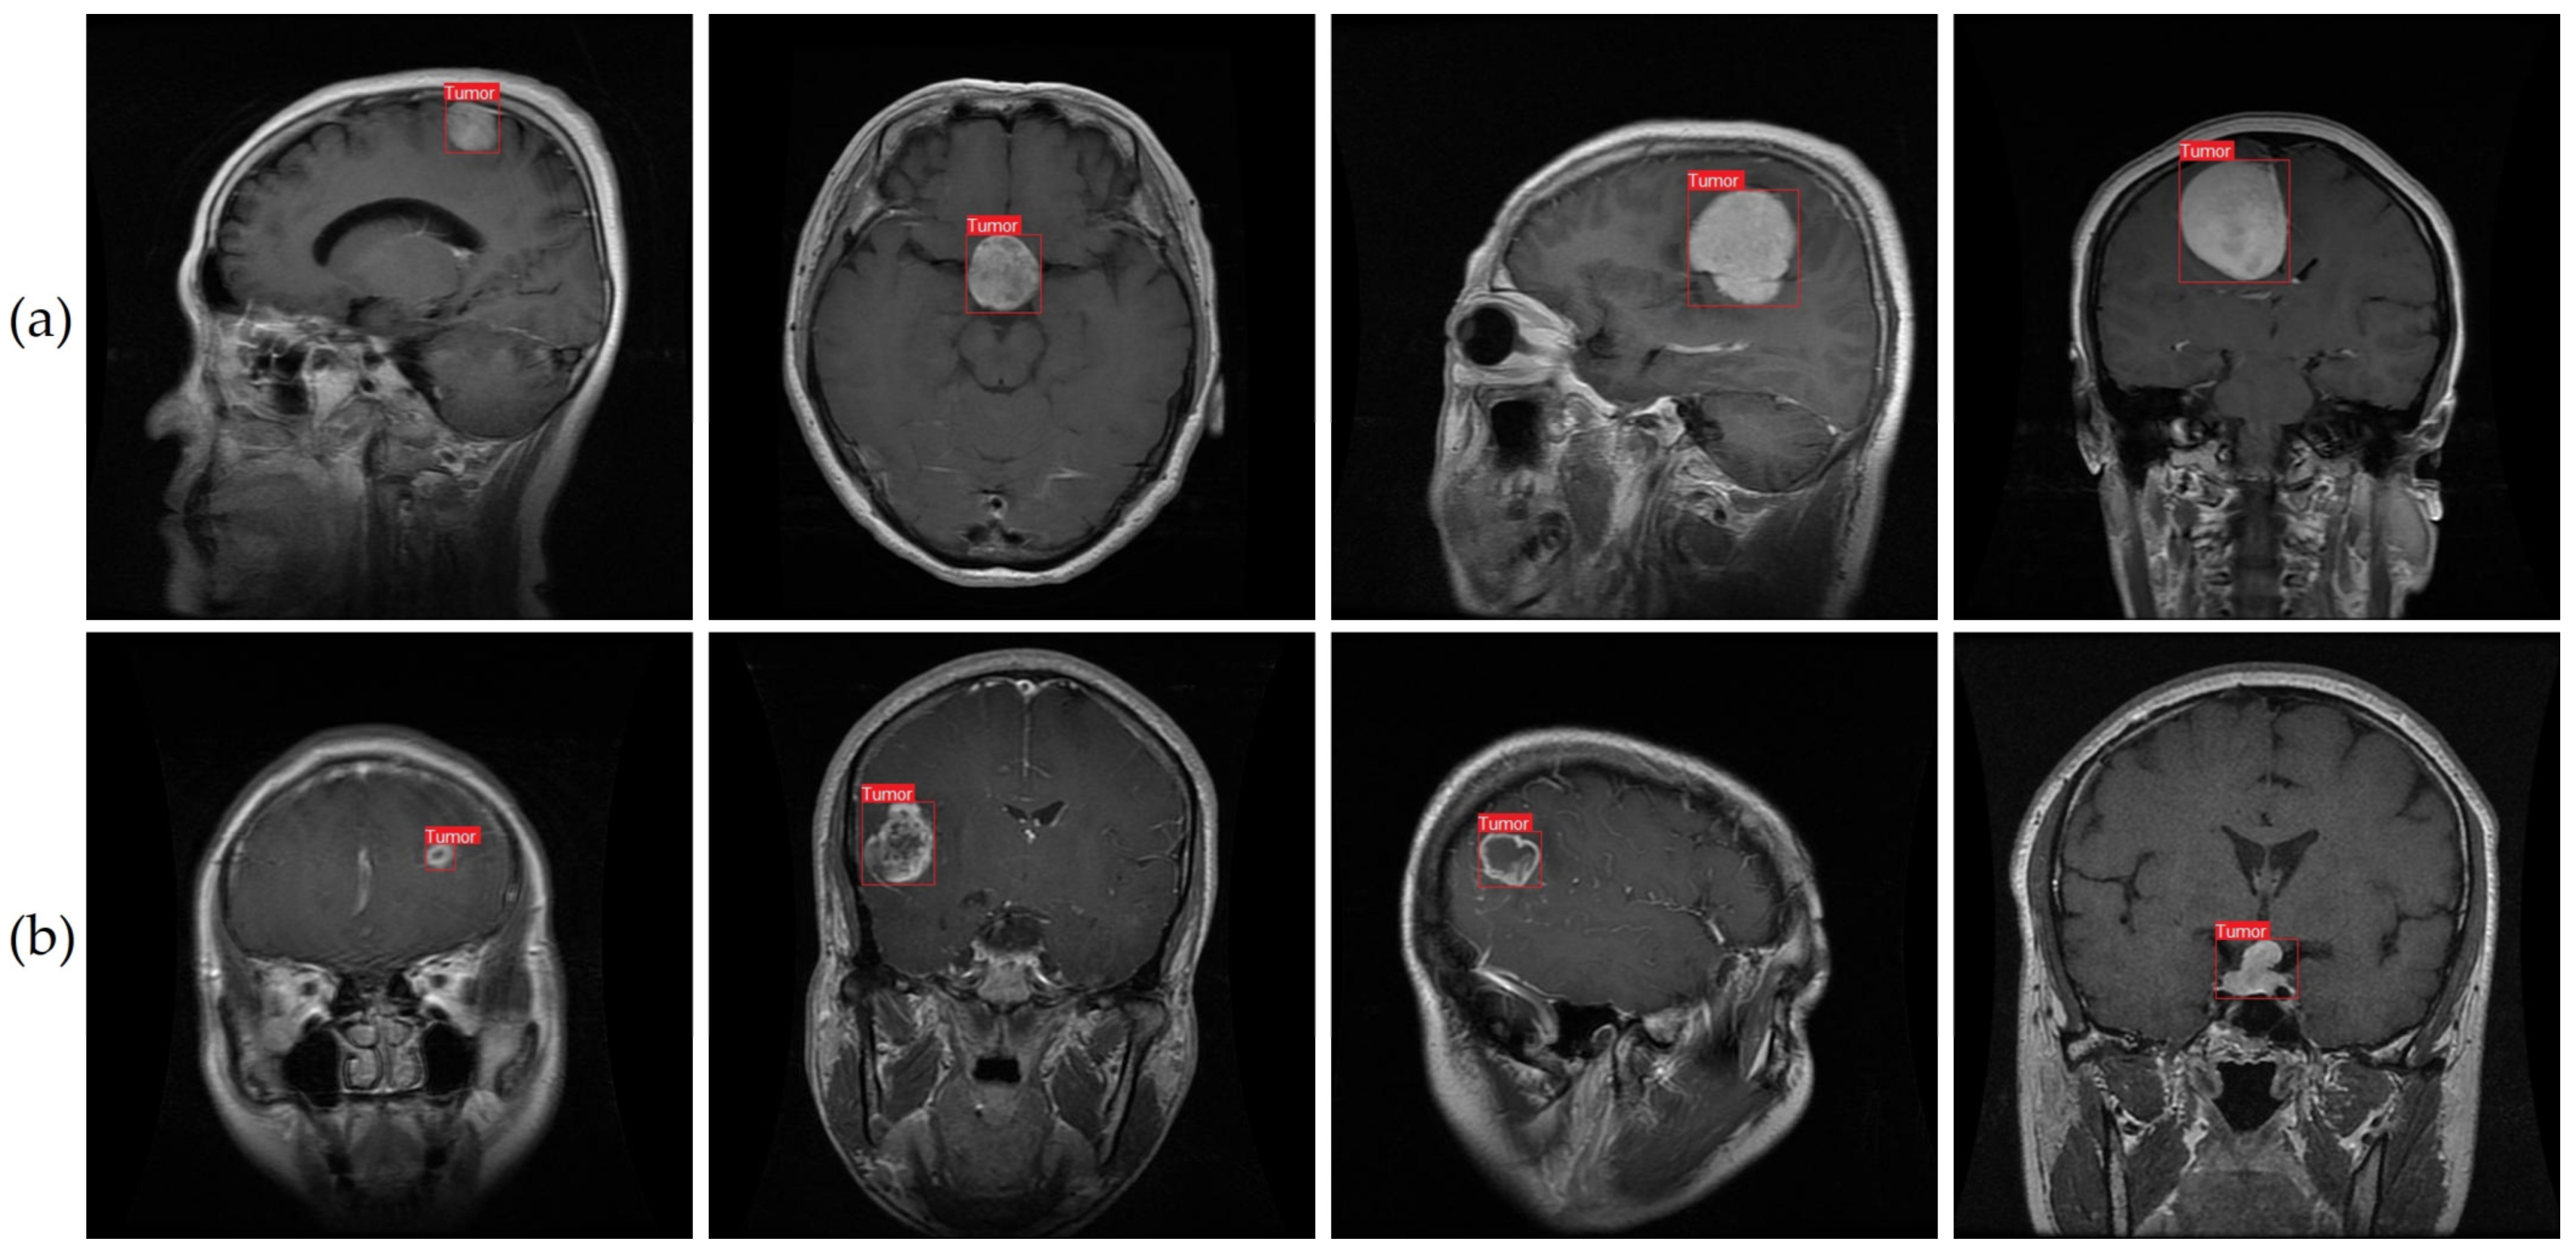

As seen in Figure 1 and described in [9], meningioma, glioma, and pituitary tumors are the most frequent primary brain tumors seen in clinical practice. Most cases of meningioma arise near the meninges tissues on the periphery of the brain or spinal cord [10]. This benign tumor develops in the membranes that rescue the brain and spinal cord. However, glioma, the brain tumor with the highest fatality rate [11], develops from the glial cells that surround and support the neurons. About a third of all cases of brain tumors are gliomas. Benign pituitary tumors develop inside the pituitary gland [12]. Prognosis and treatment options for brain tumors depend on a correct diagnosis. However, conventional biopsy techniques are painful, time-consuming, and fraught with inaccuracy in sampling [13,14]. Histopathological tumor grading (Biopsy) has its own set of problems, including intra-tumor heterogeneity and differences in the subjective assessments of different experts [15]. The diagnostic process for tumors is made more difficult and restrictive by these characteristics.

To ensure the validity of our findings, we used an openly available MRI dataset obtained from kaggle.com [64,65]. MRI scan images are included in this collection, since they are the gold standard for diagnosing brain tumors. Glioma (2548 images), pituitary (2658 images), meningioma (2582 images), and no tumor (2500 images) were the four subsets that made up our dataset of brain tumors. Images were all scaled to 512 pixels on the horizontal and vertical dimensions. We used 8232 MRI images (or 80% of the dataset) for training in our analysis, whereas 2056 MRI images (or 20% of the dataset) were set aside for testing. Brain tumor photos from various categories are shown as examples in Figure 1. For each type of brain cancer (glioma, pituitary, and meningioma), Table 1 provides the number of pictures in various views such as axial, coronal and sagittal. It is important to keep in mind that medical photos, in contrast to natural images, are more complicated and necessitate a greater level of skill to ensure appropriate analysis and interpretation. The brain tumor dataset was labeled with oversight from a medical specialist to ensure precision and consistency. This physician’s expertise was crucial, as it established criteria for how the dataset should be labeled. However, not all brain cancers have characteristic imaging findings; therefore, depending entirely on image analysis can be risky. As a result, pathology analysis is essential for diagnosing brain cancers. Our dataset featured abnormal language descriptions annotated by a medical expert to give rich context for model training. A larger amount of training data aids in the creation of more reliable models. Data augmentation strategies can be used to increase the diversity of the training samples when the volume of available data is low. To improve a model’s generalizability, data augmentation can be used to generate new variants of the existing data. In conclusion, our model’s predictive power was enhanced by the incorporation of extensive labeled data, curated by medical experts. To further improve the prediction models’ accuracy and reliability, data augmentation techniques can be used to increase the diversity of the training samples.

We conducted qualitative research to supplement our quantitative evaluation of our suggested technique for identifying brain tumors from MRI. To do this, we selected six MRI images from our dataset. As can be seen in Figure 11, using the improved YOLOv7 model yielded consistent and trustworthy outcomes across both classes. The situations and conditions depicted in the chosen photos covered the various range of brain tumor cases. The model’s consistent execution across a variety of settings suggests that it might be useful in monitoring and detecting brain tumors using MRI.

Previous research has struggled with the correct recognition of small brain tumors in pictures. We attempted to enlarge the dataset and enhance the accuracy of tumor detection by collecting images of brain tumors of varying sizes. In Figure 11b, examples of the smaller brain tumors that were part of our dataset can be seen. We took a cue from prior work [9] and implemented a method for accurately detecting tiny objects while still retaining fine details. The method includes merging a smaller-sized feature map with a larger-scale feature map from a higher layer. The large feature map can recognize tumor pixels of various sizes using a combination of location data from lower levels and sophisticated property data from upper layers.

Figure 11 shows that our suggested method, which employs the improved YOLOv7 model, is highly successful at detecting brain cancers under a variety of conditions. Images of both large and small tumors were used to test the consistency of our method. For effective prevention and treatment of brain cancers, early diagnosis is essential [81,82,83,84,85]. Our method successfully reduces false detections while maintaining high accuracy in locating microscopic tumor areas in pictures. Our results indicate that our proposed method shows promise as a tool for facilitating diagnosis of brain tumors and enhancing patient outcomes.

This study introduced an enhanced YOLOv7 model for accurately detecting multiclass brain tumors, specifically meningioma, glioma, and pituitary tumors, as visually depicted in Figure 1 and Figure 11. Our proposed model was carefully optimized, incorporating the CBAM attention mechanism and the SPPF+ and BiFPN components. The model was trained by employing MRI images acquired through T1-weighted contrast-enhanced sequences, harnessing the enhanced anatomical insights facilitated by contrast agents.